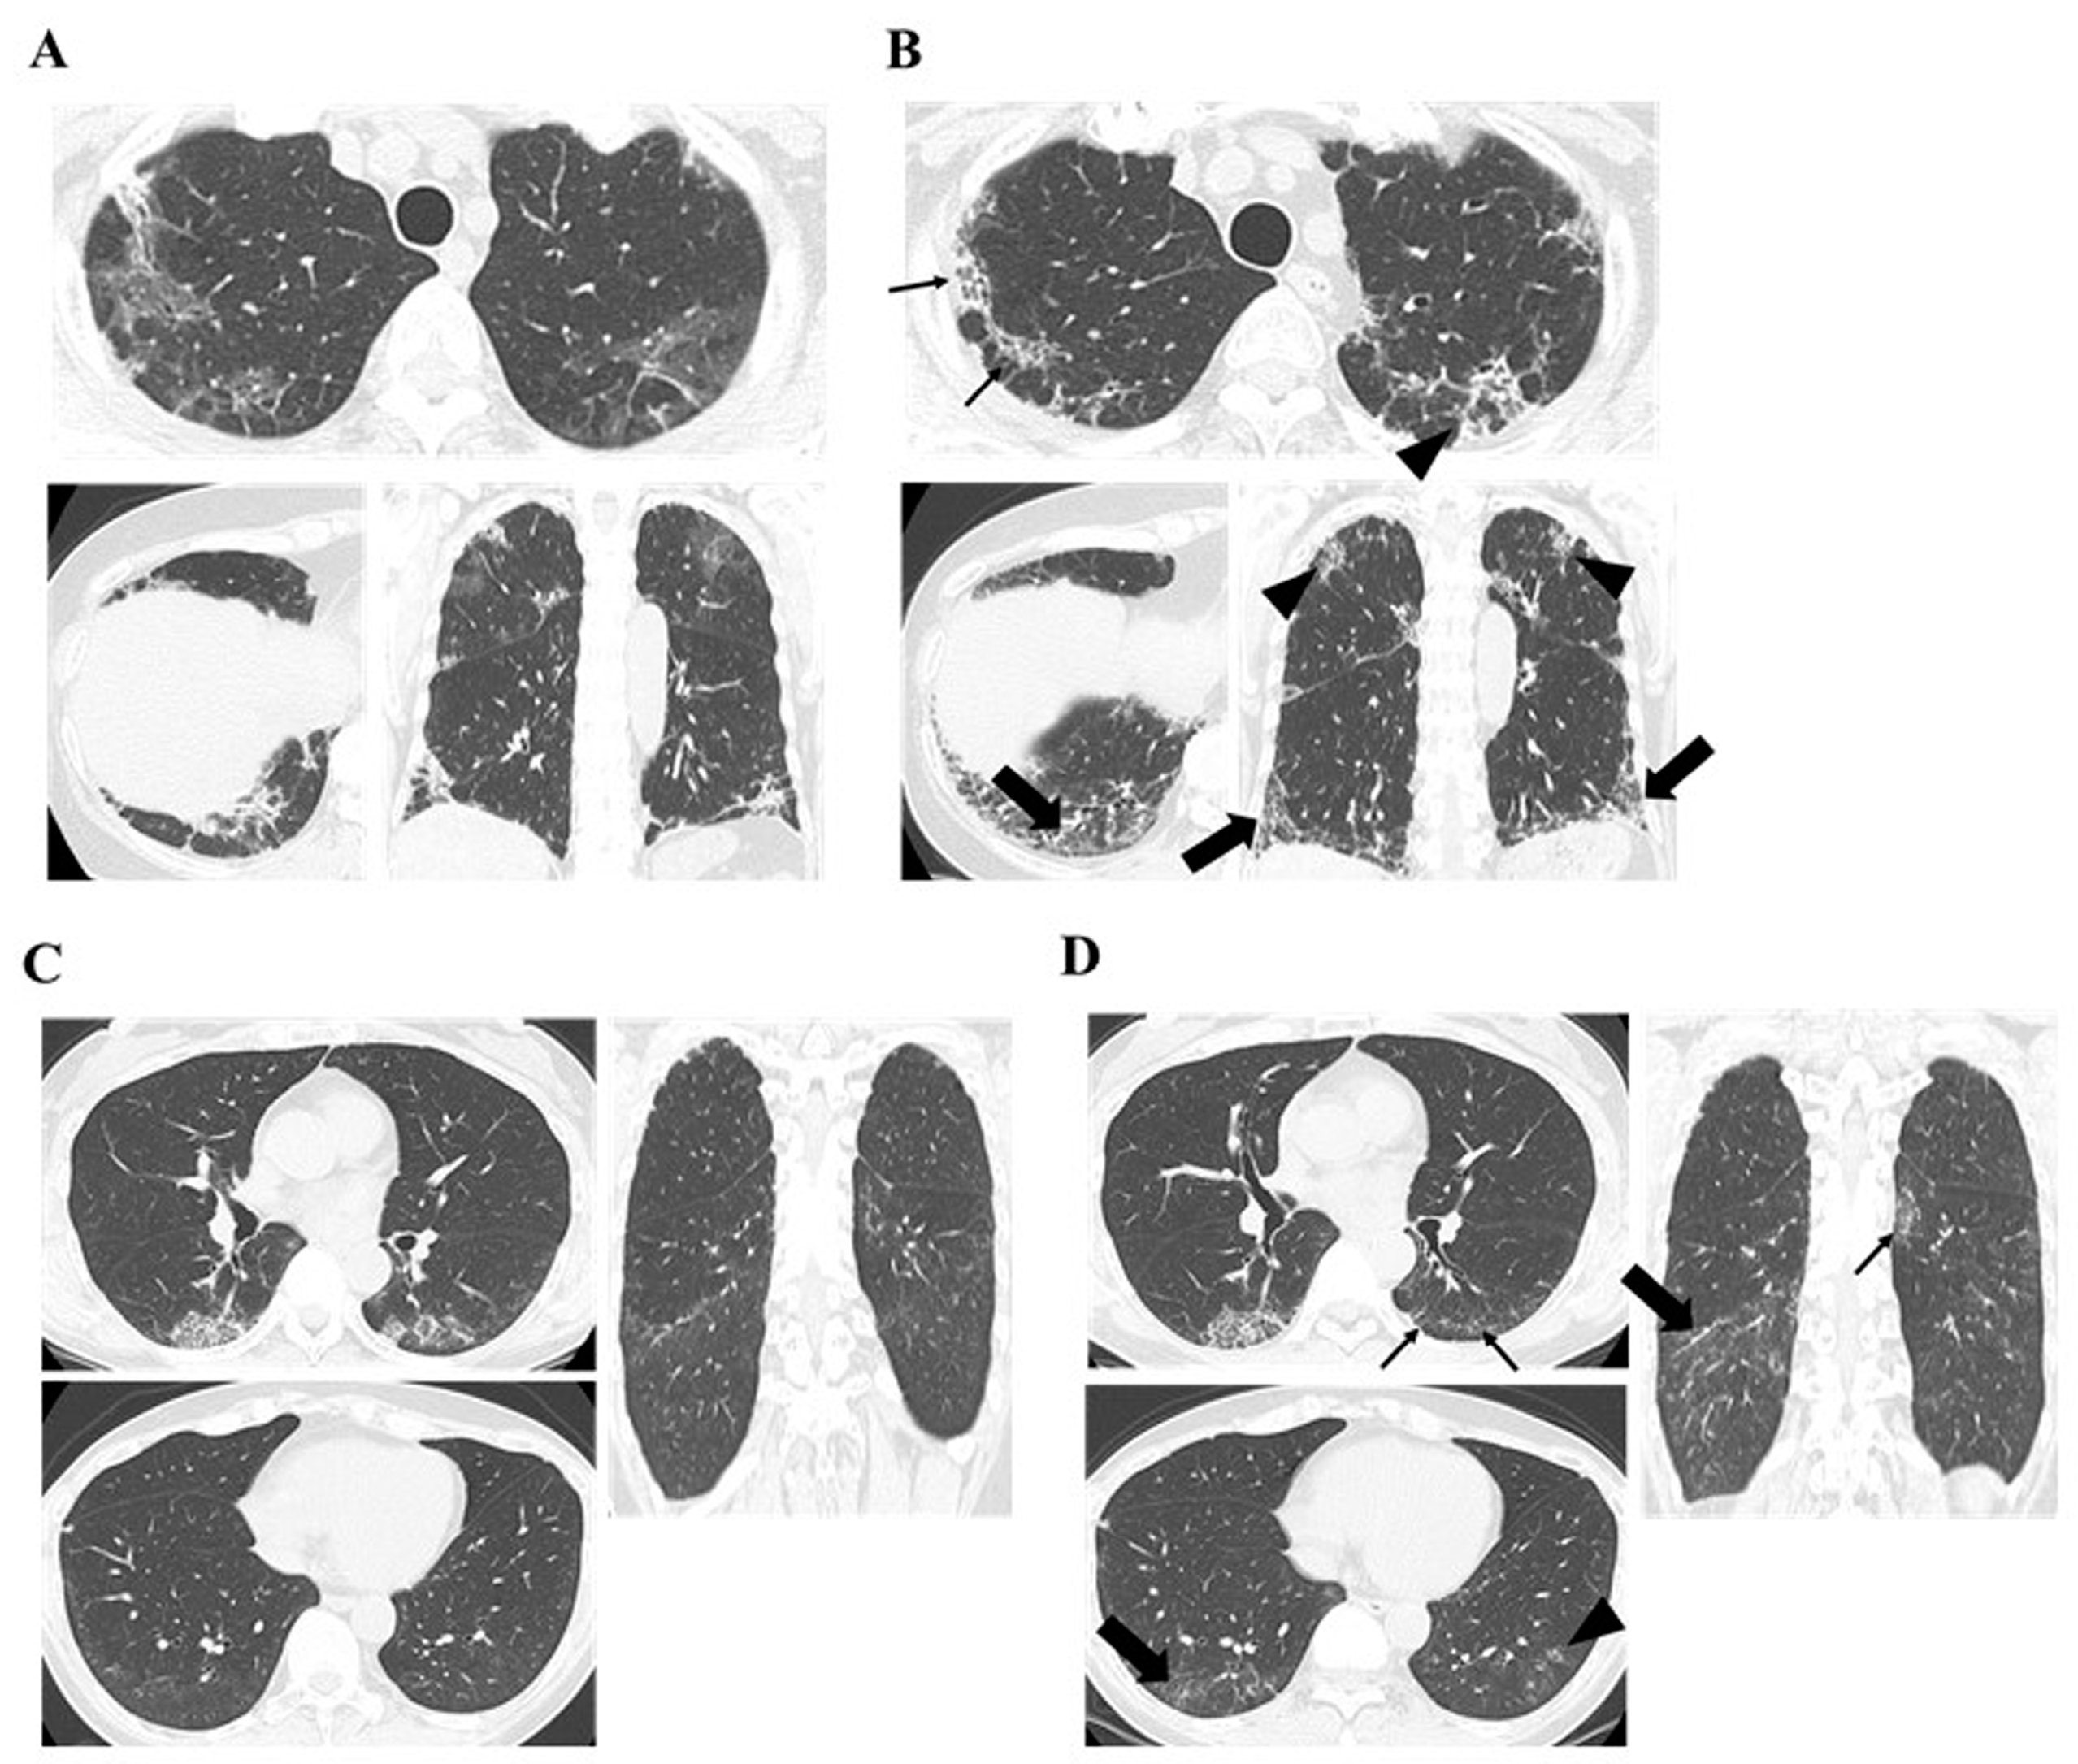

| Chest HRCT Findings of PPF | Anti-MDA5-Ab Negative (n = 9) | Anti-MDA5-Ab Positive (n = 5) | p-Value | |

|---|---|---|---|---|

| Increased extent or severity of traction bronchiectasis and bronchiolectasis | n (%) | 8 (88.9) | 5 (100) | 1 |

| months | 13.9 (7.2–19.5) | 3.3 (0.3–5.2) | 0.016 | |

| New ground-glass opacity with traction bronchiectasis | n (%) | 7 (77.8) | 5 (100) | 0.51 |

| months | 14.6 (6.0–32.3) | 3.3 (0.3–5.2) | 0.023 | |

| New fine reticulation | n (%) | 6 (66.7) | 3 (60) | 1 |

| months | 15.8 (4.9–42.1) | 4.8 (3.3–5.7) | 0.16 | |

| Increased extent or increased coarseness of reticular abnormality | n (%) | 6 (66.7) | 2 (40) | 0.58 |

| months | 14.2 (9.5–33.6) | 5.2 (4.8–5.7) | 0.067 | |

| New or increased honeycombing | n (%) | 3 (33.3) | 0 (0) | 0.26 |

| months | 40 (33.9–71.6) | |||

| Increased lobar volume loss. | n (%) | 1 (11.1) | 2 (40) | 0.51 |

| months | 6 | 3.1 (0.4–5.7) | 0.54 |